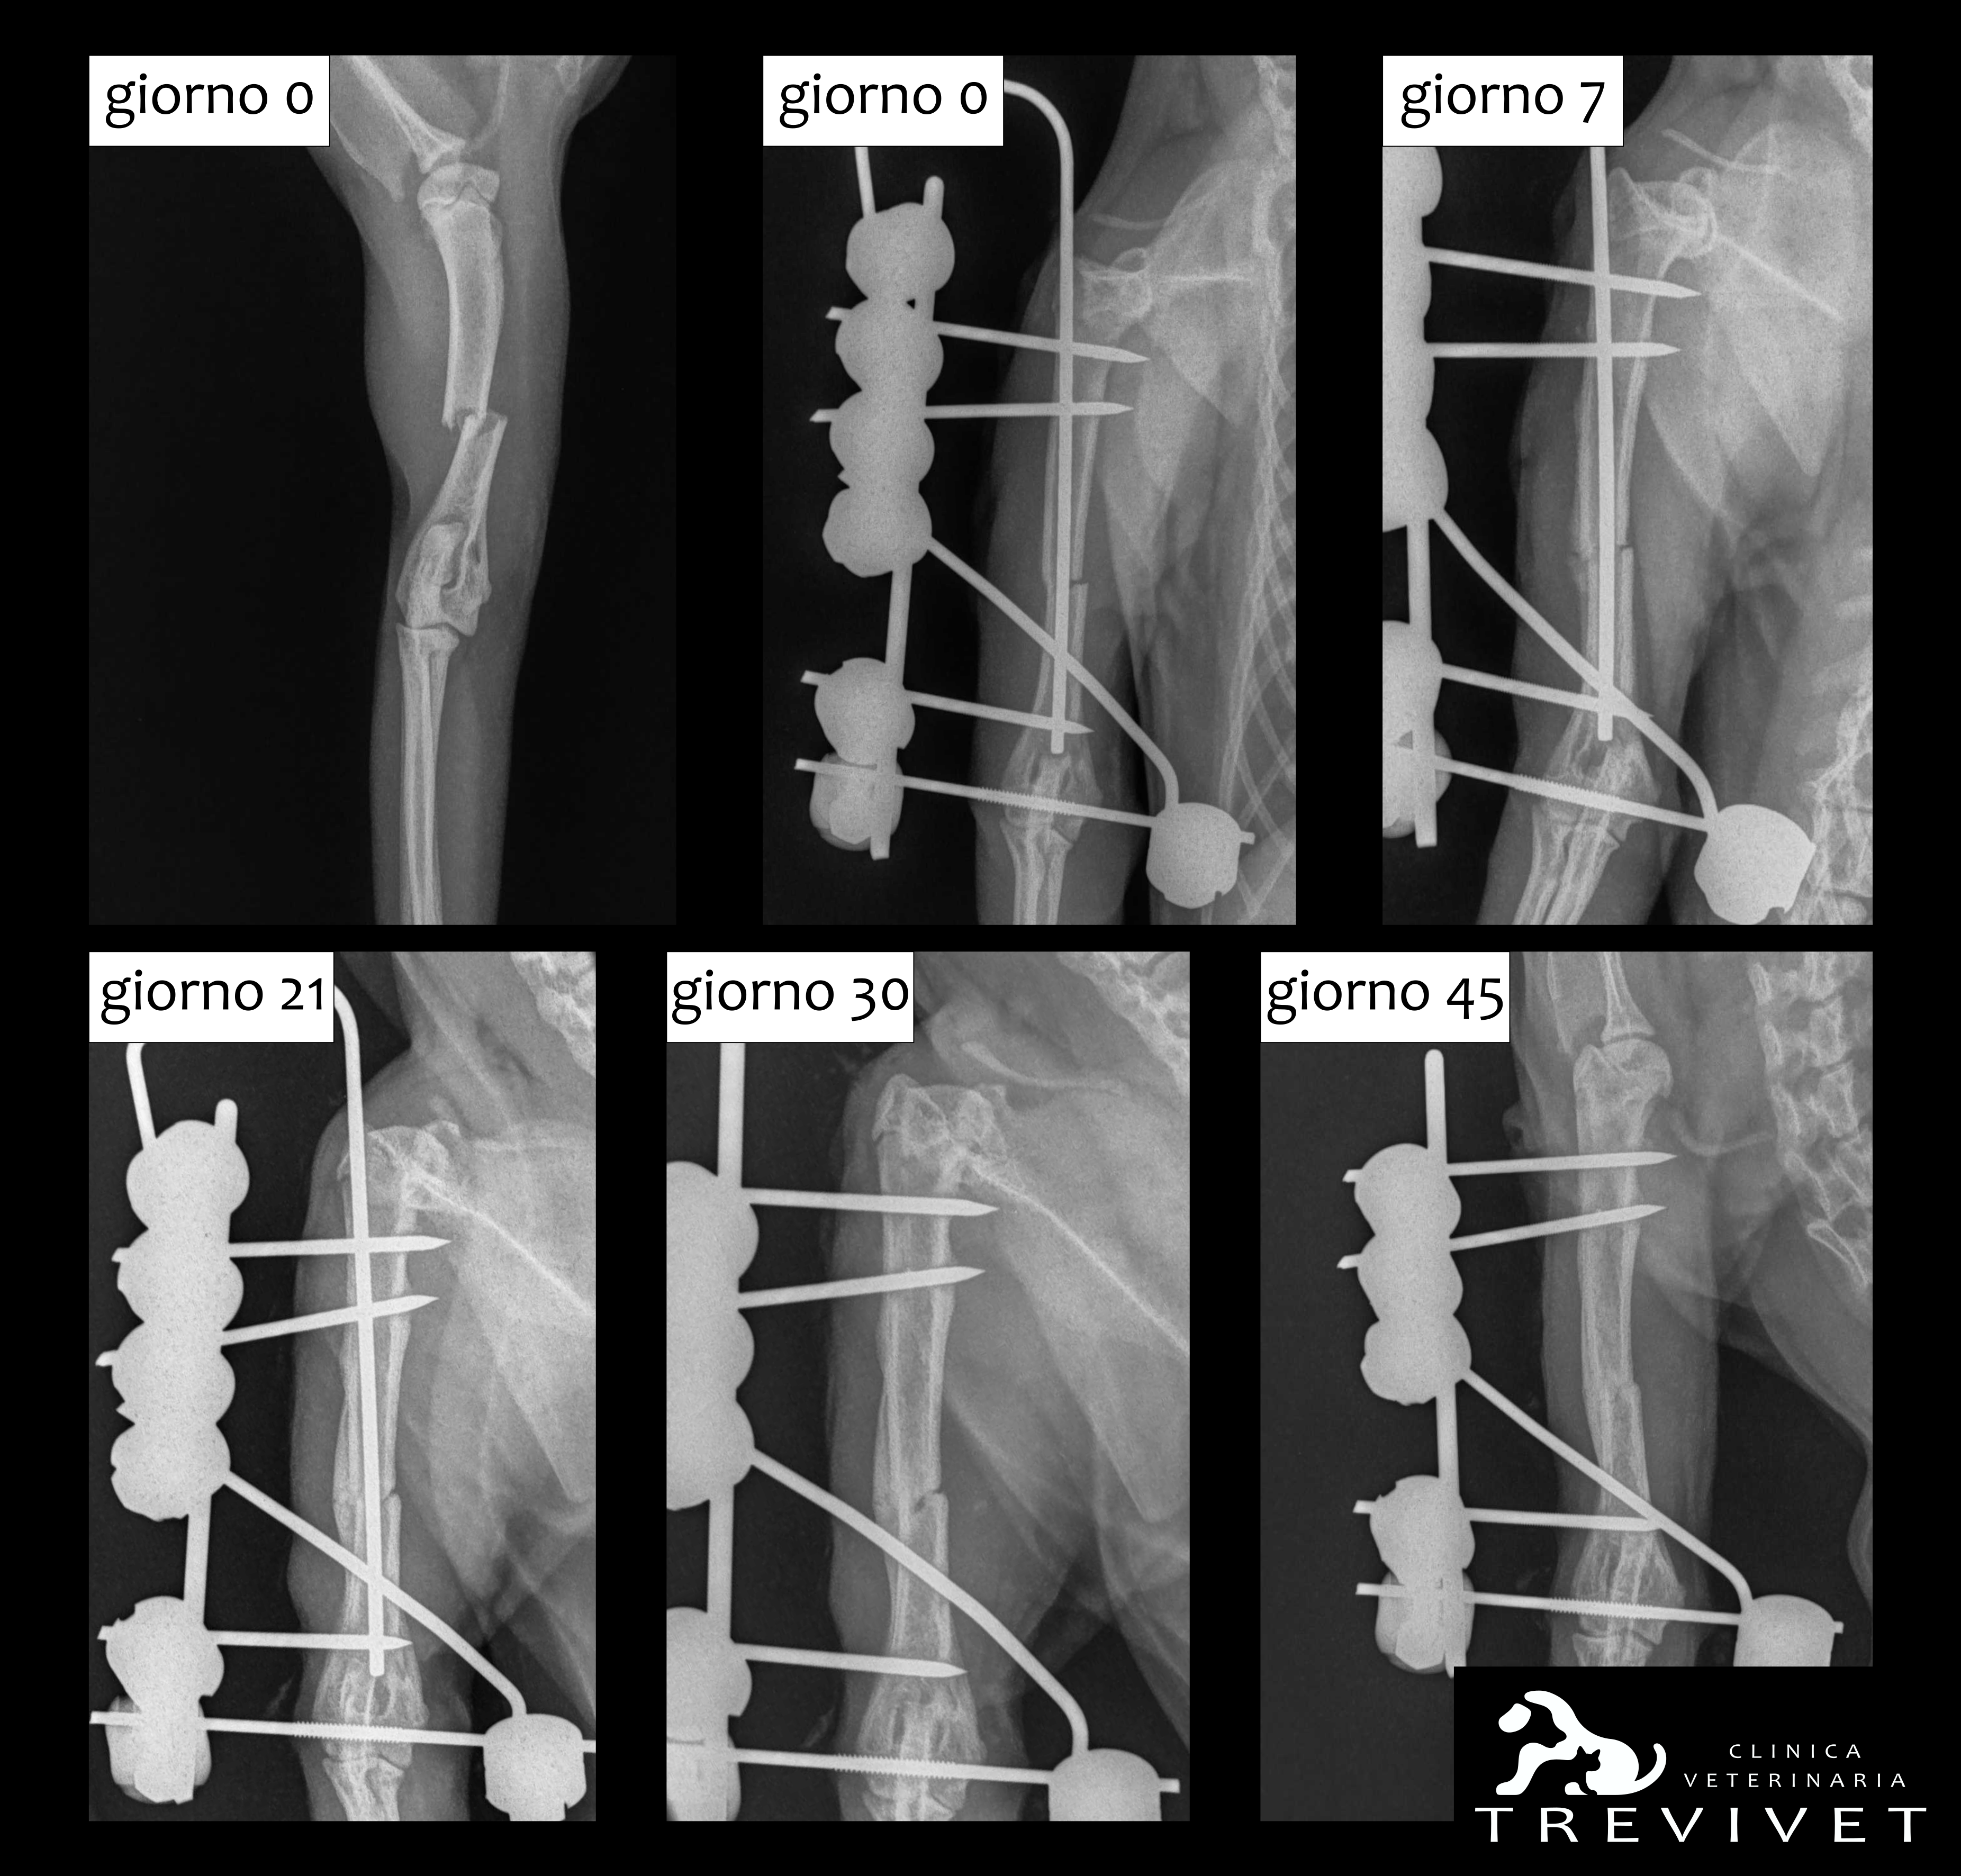

In accordo coi proprietari si decide di effettuare una riduzione chirurgica della frattura, con stabilizzazione del segmento osseo attraverso l’utilizzo di un fissatore esterno TIE-IN mono-planare bi-laterale (tipo IIA) formato da chiodi di Kirshner filettati, collegati a un barra in acciaio con morsetti Mainard e viene aggiunta una barra antirotazionale. Durante l’intervento viene utilizzata la tecnica OBNT (open but not touch), in quanto il focolaio di frattura è direttamente sottostante alla proiezione del nervo radiale (importante per l’innervazione del tratto distale del braccio e della mano), in modo da visualizzare il focolaio di frattura e il decorso del nervo, per preservarne l’integrità anatomica. La gattina viene dimessa dopo 1 giorno di ricovero con la prescrizione di mantenerla confinata per evitare eccessivo movimento dell’arto interessato e con terapie antibiotiche e antidolorifiche. Vengono effettuati controlli regolari a distanza di 10-15 giorni per valutare la stabilità dell’impianto e il proseguo della guarigione ossea.

A distanza di 4 settimane dall’intervento si decide di alleggerire l’impianto, per spostare parte delle forze di carico sul callo osseo in formazione e favorirne la “maturazione”. Dopo altre 2 settimane il callo osseo viene giudicato adeguatamente solido e si procede alla rimozione dell’impianto, si consiglia di mantenere Favy per altre 2 settimane a riposo. La ripresa di Favy è stata piena e soddisfacente sia dal punto di vista clinico-ortopedico che di qualità di vita.